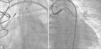

The coronary angiography showed a dilated saphenous vein graft connected to the great cardiac vein, with significant dilation of the coronary sinus (Figure 1A).

Coronary angiography confirmed the presence of the saphenous vein connection with the great cardiac vein, with additional evidence of segmental and severe obstructive lesion in the mid-third of the nonrevascularized left circumflex artery (Figure 1B). We chose to perform a percutaneous coronary intervention (PCI) of the left circumflex artery and outpatient programming for the AVF occlusion. Everolimus-eluting stenting was performed successfully using a 2.75×33mm Xience Prime® stent (Abbott Vascular, Santa Clara, United States).